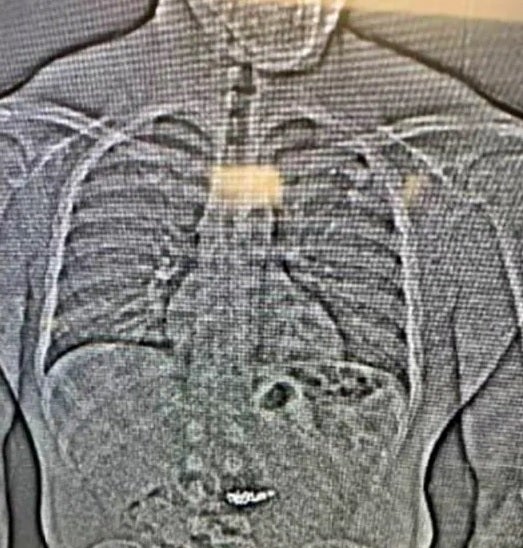

Dann griff der Mann dem Polizeibericht zufolge zu und riss die kostbaren Stücke an sich. Ein Angestellter versuchte demnach noch, ihn aufzuhalten – vergeblich. Der mutmaßliche Täter konnte mit einem Fahrzeug fliehen. Die Ermittler kamen ihm jedoch auf die Spur und nahmen ihn fest. Offenbar in letzter Verzweiflung soll er die Ohrringe daraufhin kurzerhand verschluckt haben. Der Verdächtige wurde wegen Raubes und schweren Diebstahls angeklagt.